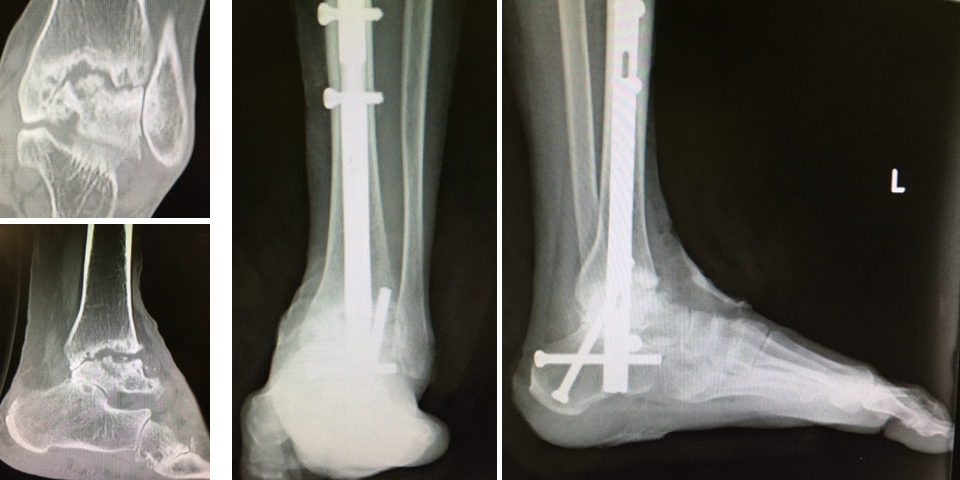

OA、RAの足関節障害には人工足関節置換術(total ankle arthroplasty: TAA)(図9)や関節固定術を行います。TAAは距踵病変がなく、比較的変形の少ない例に施行され、可動性を保つことができます。固定術は高度変形にも適応があり、関節の安定化が期待できます(図10)。RAは距踵関節にも破壊が生じやすいため、距腿関節と距踵関節(Tibio-talo-calcaneal: TTC)を同時に逆行性髄内釘で固定することもあります(図11)。

図9:人工足関節置換術

図10 足関節固定術

図11 RAの足関節障害に対するTTC固定術